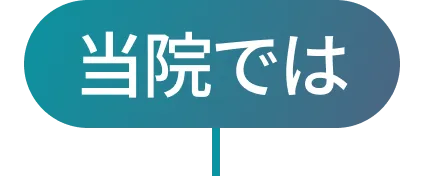

身長が伸びる強さには個人差があります。

「成長ホルモン」と「栄養補充」で治療することで身長を伸ばすことができます。

身長が伸びる期間の長さにも個人差があります。

思春期コントロール治療をすることで、身長が伸びる期間を伸ばすことができます。

身長の伸びる力を

身長の伸びる力を

本来体内で生成される成長ホルモンを、注射で外部から補充する治療方法です。身長が伸びる速度が向上する最も効果が期待できる方法です。

成長ホルモンの作用に影響する鉄、亜鉛、ビタミンDなどの栄養は不足しがちなため、サプリメントでの補給が身長の伸び率維持に役立ちます。

ホルモンの働きを調整することで、思春期の進行を緩やかにして、身長が伸びる期間を長く保てるようにします。